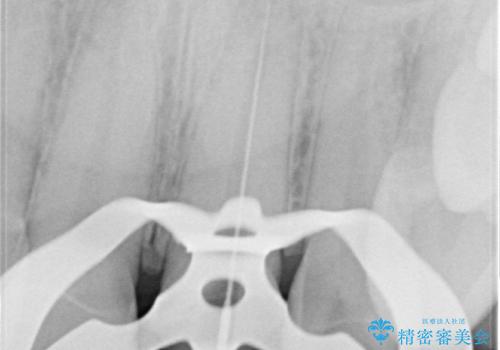

精密根管治療では、菌を入れない環境を作り見逃しが無いようにマイクロスコープを使って治療する事が大切です。

まだ誰も触っていない根管ならばほとんどのケースで治せる事が出来ます。